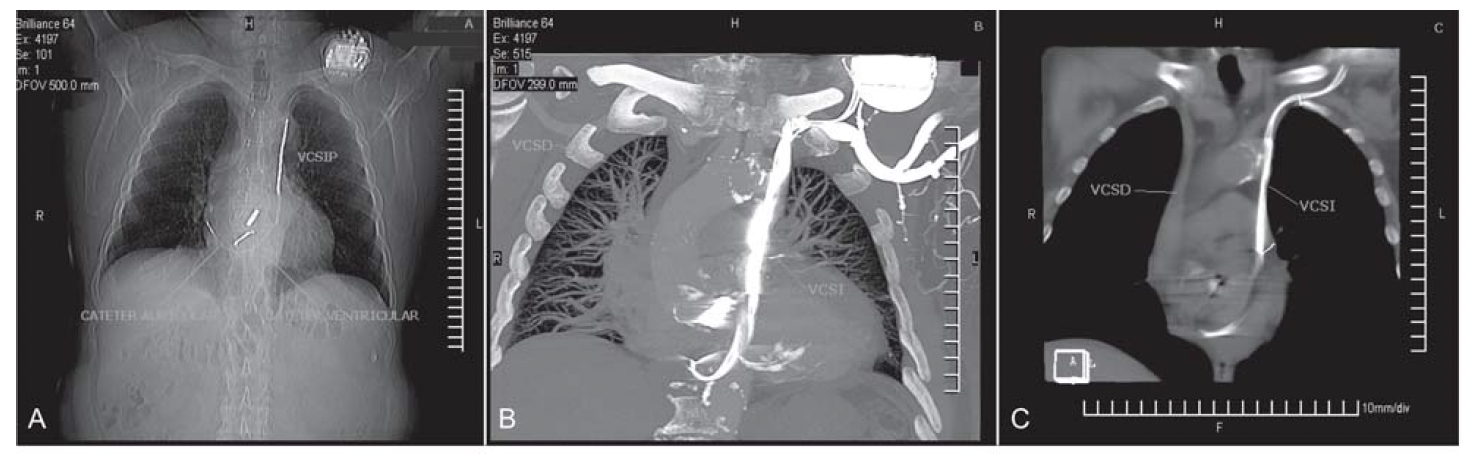

La vena cava superior izquierda persistente (VCSIP) es la anomalía congénita venosa del tórax más frecuente. Se encuentra en el 0,3% de la población general y en el 5-10% de los pacientes con cardiopatías congénitas. Generalmente evoluciona en forma asintomática y no genera trastornos hemodinámicos, pero su reconocimiento es importante, ya que puede dificultar la introducción de catéteres para mediciones hemodinámicas, los implantes de marcapasos cardíacos (MCP) y de cardiodesfibriladores automáticos implantables (CDAI), especialmente cuando se utiliza la vía cefálica o la subclavia izquierda. En el caso clínico que se presenta se efectuó el implante de un CDAI bicameral vía VCSIP, descubierta durante el procedimiento. Asimismo, se muestran las características de esta variedad anatómica mediante tomografía cardíaca computarizada de 64 cortes (TCC64).